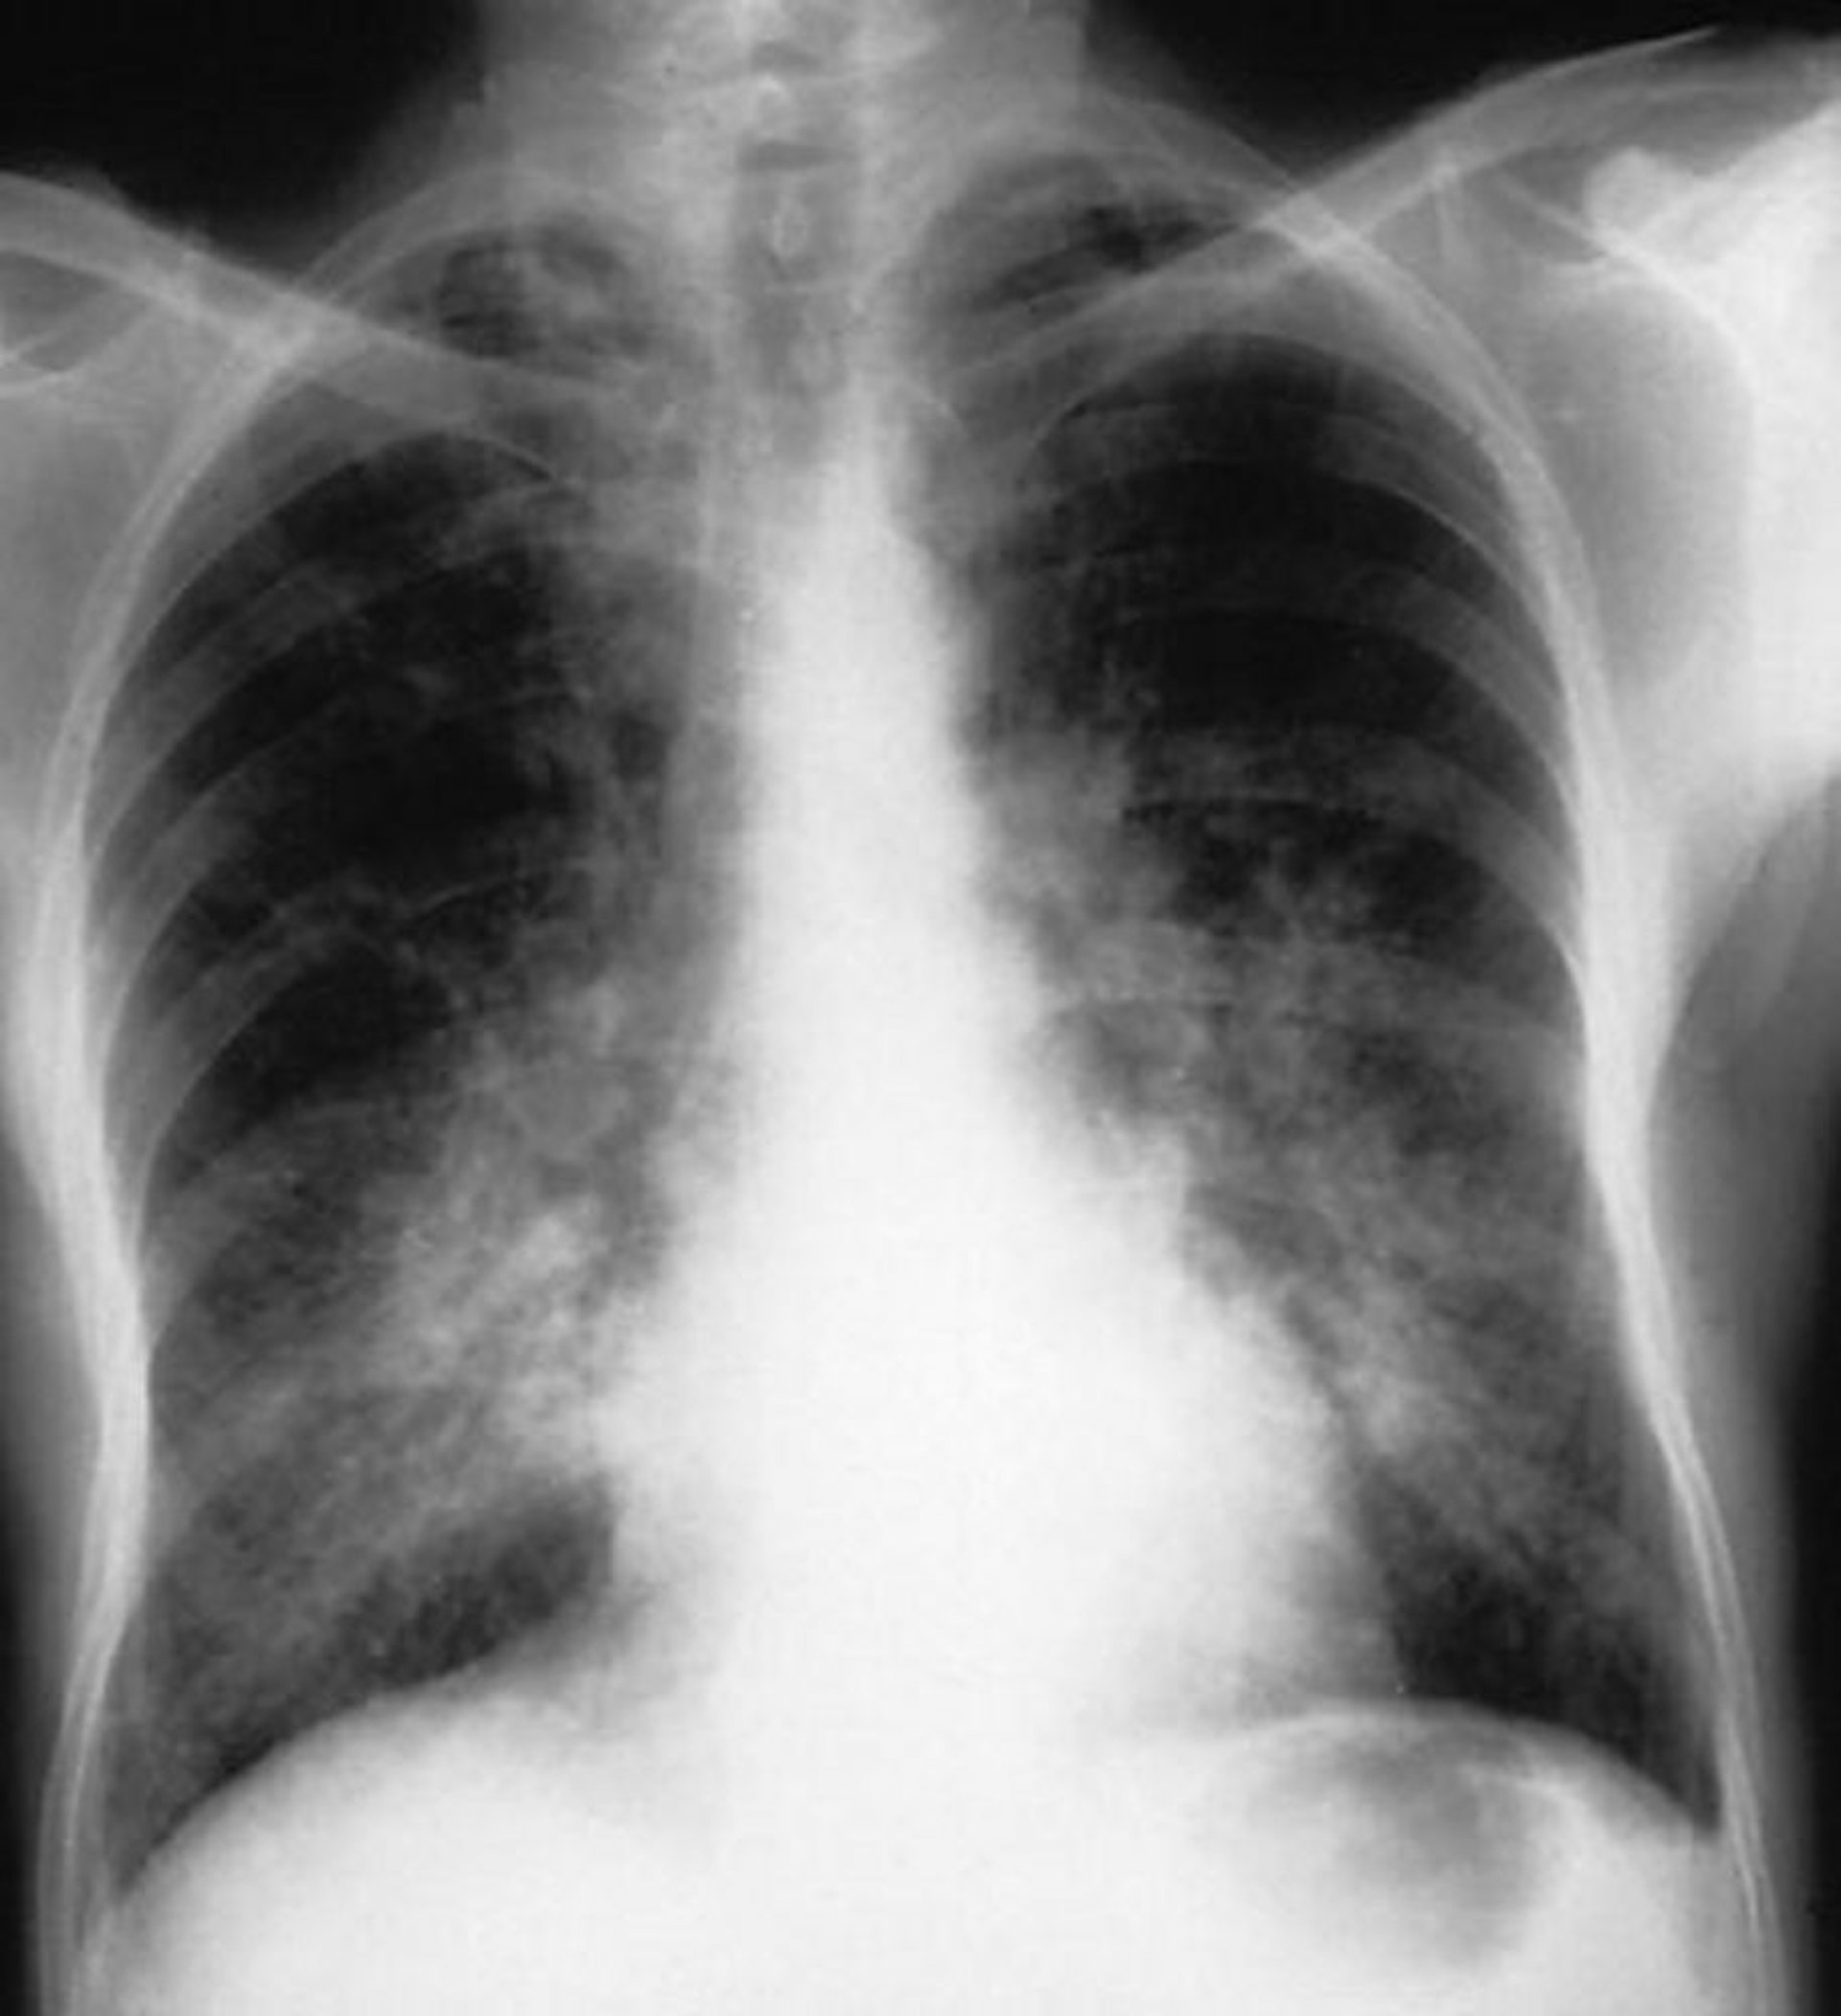

喀血が最も顕著な症状である;しかしながら,肺胞出血がある患者に喀血が生じないこともあり,胸部X線上の浸潤影のみである場合もあれば,浸潤影に加えて呼吸窮迫,呼吸不全,またはその両方を呈することもある。

By permission of the publisher. From Cohen A, Glassock R.In Atlas of Diseases of the Kidney: Glomerulonephritis and Vasculitis.Edited by R Schrier (series editor), RJ Glassock, and AH Cohen.Philadelphia, Current Medicine, 1999.

最大で患者の40%に肉眼的血尿を認めるが,肺出血は週単位から年単位で腎症状に先行しうる。